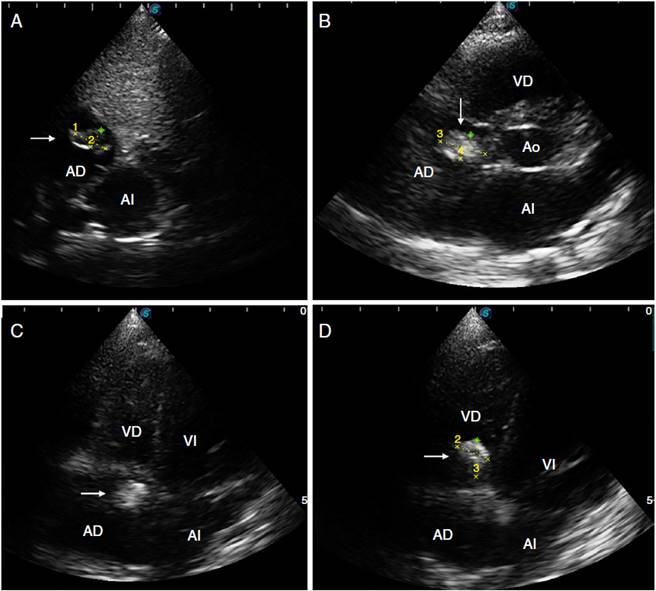

Fue referida al servicio de Cardiología pediátrica para evaluación previo inicio de su programa de rehabilitación neurológica. La madre la refería asintomática cardiovascular, con una clase funcional I de Ross. A la exploración física se detectaron ruidos cardiacos rítmicos, de buena intensidad y frecuencia sin soplos aparentes, s2 sin alteraciones, pulsos adecuados y llenado capilar menor a 3 segundos. Se realizó ecocardiograma transtorácico debido al antecedente de trombosis venosa cerebral y de colocación de catéter intravascular durante su estancia en terapia intensiva, encontrándose una imagen compacta hiperecogénica compatible con un trombo organizado, con diámetro máximo de 12 x 7 mm, implantado en la valva septal de la válvula tricúspide y con ligera adherencia en el ángulo formado con el tabique auricular, introduciéndose en la sístole al ventrículo derecho, sin generar obstrucción del sistema venoso o de la válvula tricúspide. No existían gradientes ni se encontró cardiopatía estructural (fig. 1).

Figura 1 Ecocardiograma transtorácico. A) Imagen subcostal que muestra una imagen hiperecogénica organizada de 12 mm x 7 mm en la aurícula derecha sugestiva de trombo cardíaco. B) Imagen de eje corto en la que se observa trombo de 10,5 x 5,9 mm adosado a la valva septal de la válvula tricúspide y al ángulo formado con el tabique auricular. C) Imagen de cuatro cámaras en que se aprecia el trombo adherido a la valva septal de la válvula tricúspide y en el ángulo formado con el tabique auricular. D) Imagen de cuatro cámaras que evidencia la apertura valvular tricúspide y el trombo ventricular derecho de 8,6 x 9,4 mm. Ventrículo derecho (VD); ventrículo izquierdo (VI); aurícula derecha (AD); aurícula izquierda (AI); aorta (Ao).